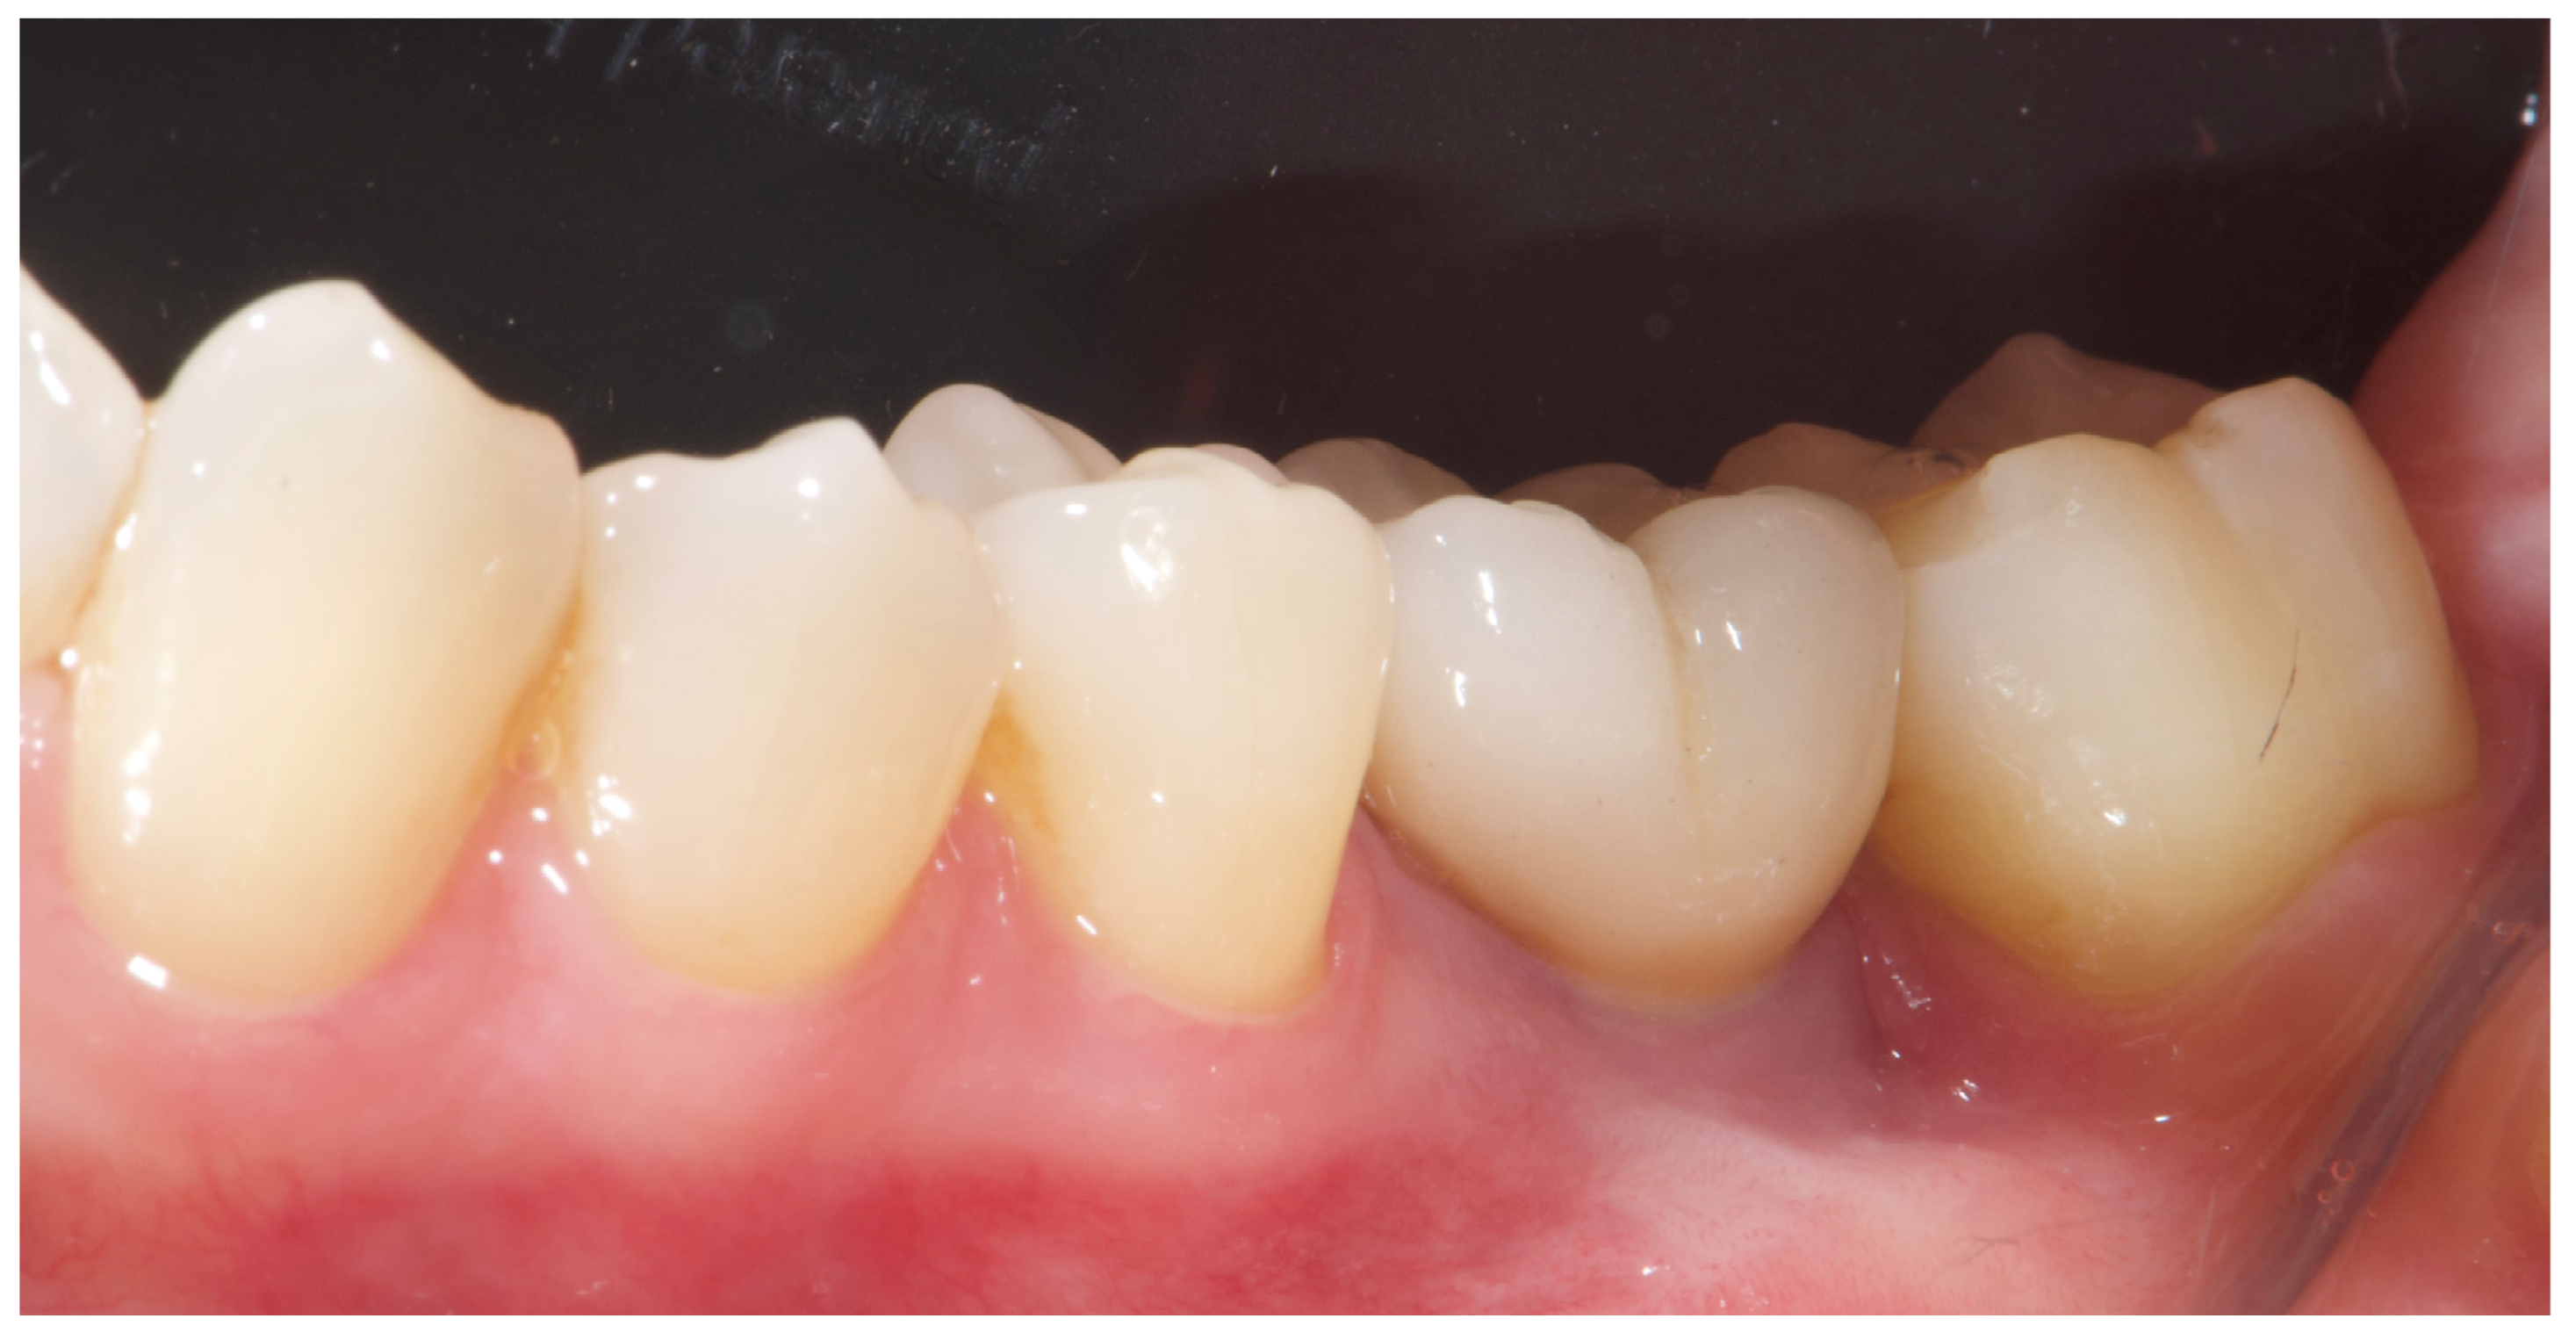

2. Case Summary